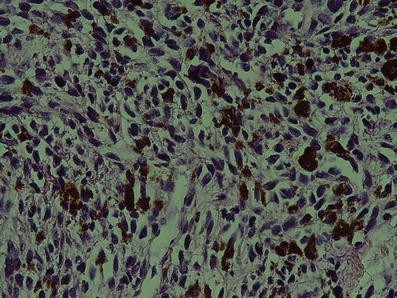

Malignant spindled or ovoid melanocytes with hyperchromatic and pleomorphic nuclei and considerable amount of melanin are present in histopathologic view